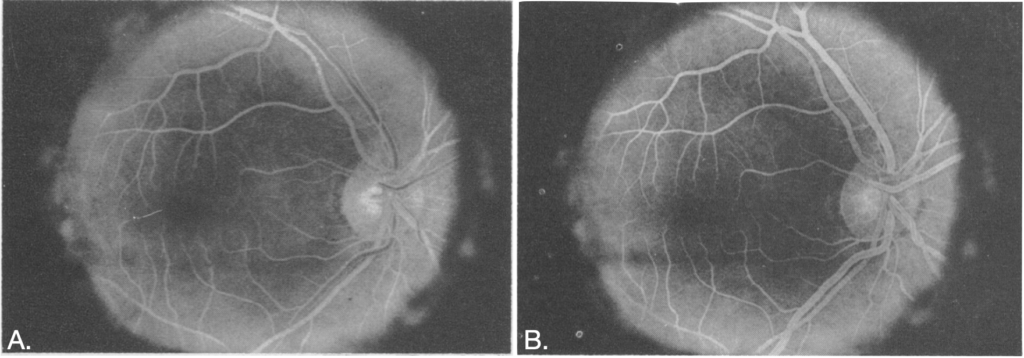

1961 – Harold R. Novotny and David L. Alvis published a practical method for studying retinal blood flow in humans using intravenous fluorescein and serial fundus photography. In their Circulation report they describe a Zeiss fundus camera with electronic flash and define the optical requirements for fluorescein imaging (blue excitation around 490 nm and green emission around 520 nm). In a darkened room they rapidly injected 5 mL of 5% fluorescein in sodium bicarbonate (Fluorescite) into an antecubital vein, and photograph the retinal circulation at 12-second intervals for ~3½ minutes. This simple method captured distinct arteriolar and venous filling phases and revealed vascular detail not readily seen with routine ophthalmoscopy or standard fundus photographs.

Later accounts note the technique was first developed in 1959 while they were medical students, trialled initially in rabbits, and that the first successful human angiogram was performed on Alvis after a coin toss.